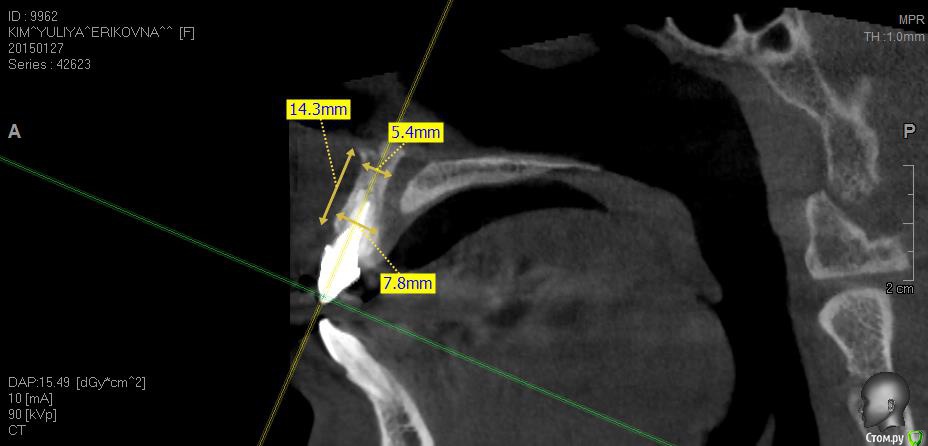

Евгений Ходыкин Опубликовано 3 февраля, 2015 Поделиться Опубликовано 3 февраля, 2015 13мм многовато будет. У Вас вестибулярно выше край кости, плюс заглубиться немного нужно будет. Либо вестибулярно остаётся несколько витков и всё это мяском перекрывается) 1 Ссылка на комментарий

Evikrol Опубликовано 3 февраля, 2015 Автор Поделиться Опубликовано 3 февраля, 2015 Значит 11,5 лучше и биоос в щель, правильно? 1 Ссылка на комментарий

колесников Опубликовано 3 февраля, 2015 Поделиться Опубликовано 3 февраля, 2015 тут уже правильно заметили,13мм-многовато. заглубитесь мм на 3. необязательно тратиться на дорогой био-ос,можно и остеопласт оставить. всёравно кортикалка частично резорбируется Ссылка на комментарий